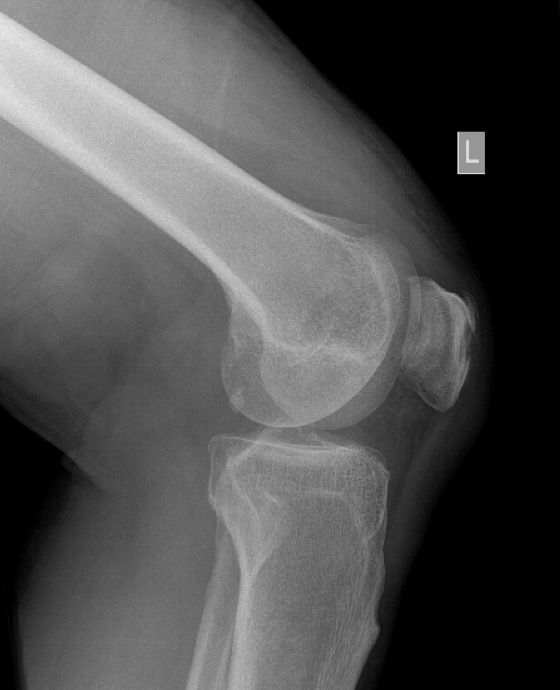

Figure 3 for case gout arthritis ( RID3567 )

Figure 3